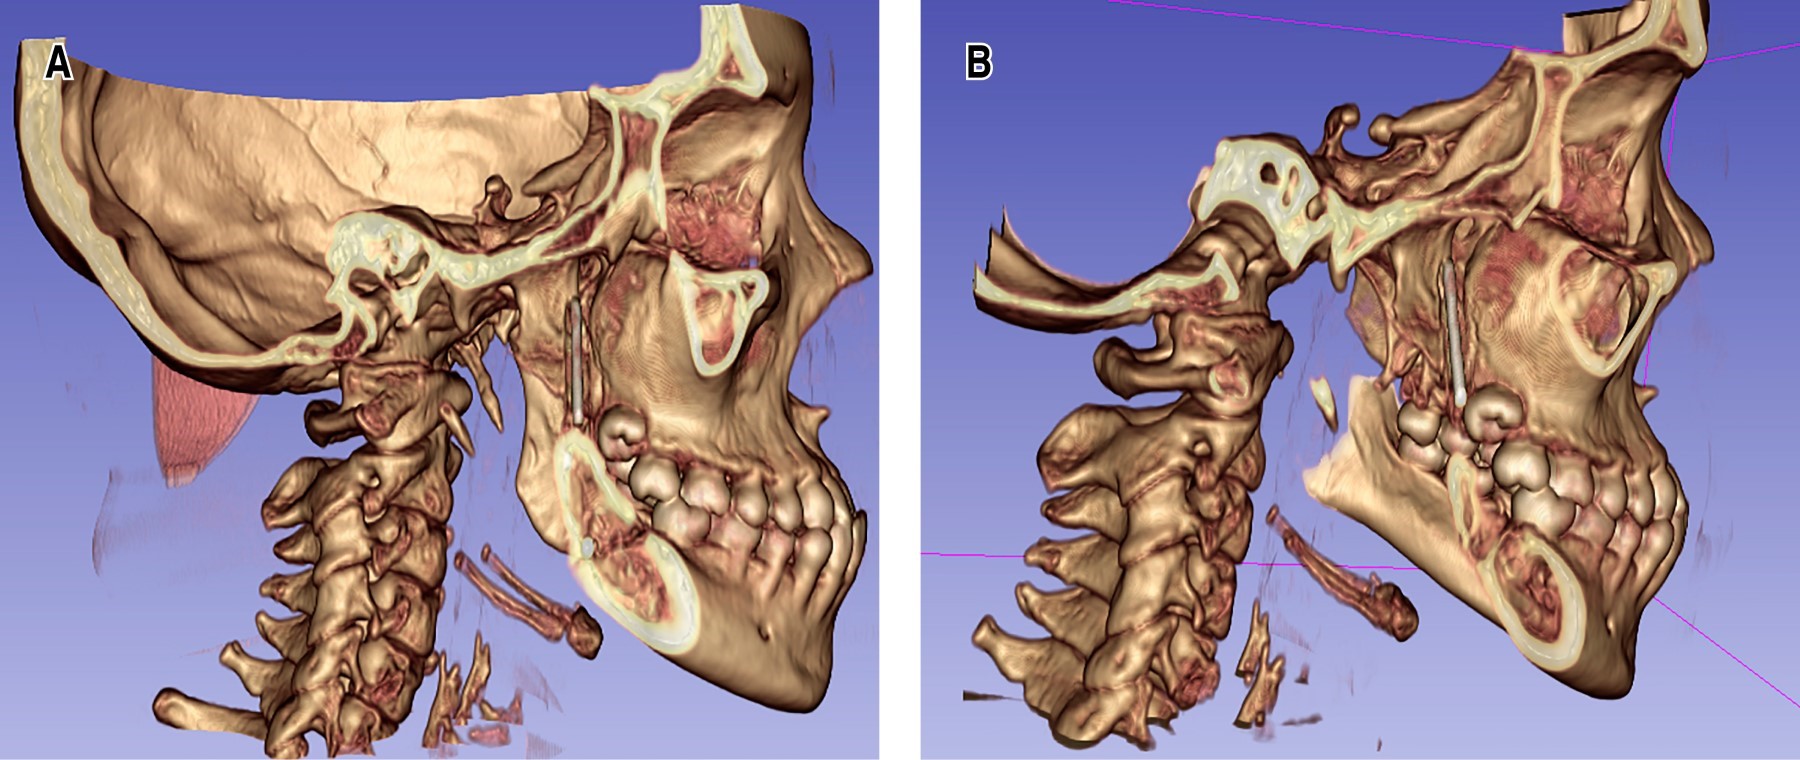

Dentro de los hallazgos imagenológicos se encontró imagen hiperdensa de forma fusiforme, de densidad similar al metal, de una longitud de 2.6 cm y un diámetro de 2 mm, esta misma se localizaba en la FP derecha, al correlacionar con el antecedente quirúrgico este CE era compatible con un fragmento de una broca percutánea del sistema 2.0; también se observan imágenes hiperdensas compatibles con una miniplaca de osteosíntesis con cuatro tornillos en ángulo mandibular, así como un área hipodensa correspondiente al trazo de fractura en proceso de cicatrización (Figuras 1 y 2).

Se realizó el retiro del CE mediante el fluoroscopio en sala de operaciones con un abordaje mínimamente invasivo en fondo de vestíbulo, pudiendo encontrar y remover exitosamente el CE de la FP derecha (Figuras 4 y 5). Posteriormente, se trató a la paciente mediante una férula miorrelajante, acompañada de fisioterapia por un lapso de cuatro meses, logrando así la recuperación de la apertura bucal, 35 milímetros aproximadamente (Figura 6). Es importante mencionar que entre el CE y los tejidos blandos circundantes se formó un área de tejido fibroso, la cual estaba condicionando la limitación de la apertura bucal. Se tomaron radiografías de control, las cuales evidenciaron la correcta consolidación de la fractura de ángulo derecho (Figura 7). Finalmente, la paciente fue transferida a ortodoncia para realizarse el tratamiento ortoquirúrgico de la maloclusión clase III.